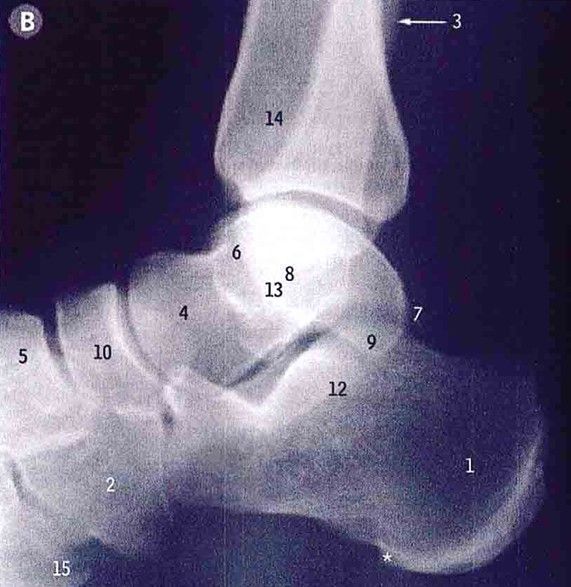

Inversion and eversion of footIdentify the Deltoid ligament, calcaneofibular ligament, posterior talofibular ligament:

Deltoid ligament (6)

Calcaneofibular ligament (3)

Posterior talofibular ligament (19)The dorsalis pedis pulse is found between the first two metatarsal bones.